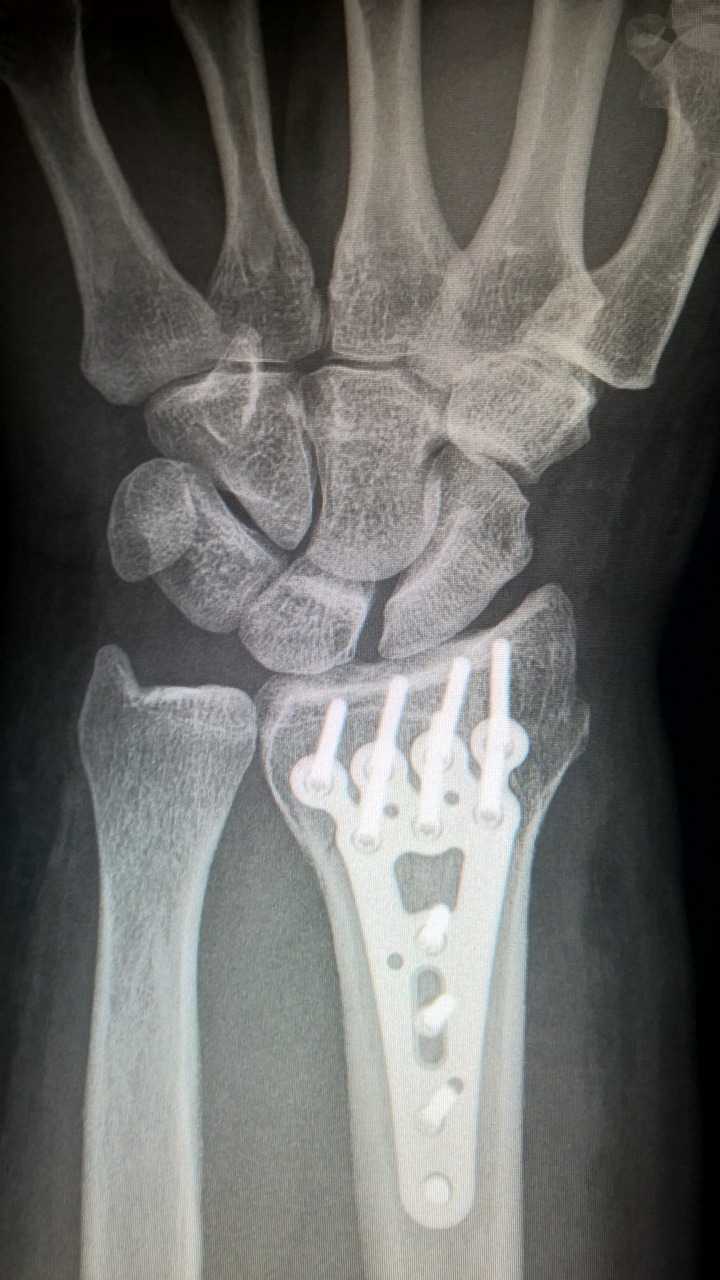

2. 수술적 치료(복잡 골절이나 불안정 골절인 경우)

- 외고정술 : 핀이나 나사를 이용해 외부에서 고정

- 내고정술 : 금속판과 나사를 이용해 내부에서 고정

- 경피적 핀 고정술 : 피부를 통해 핀을 삽입하여 고정